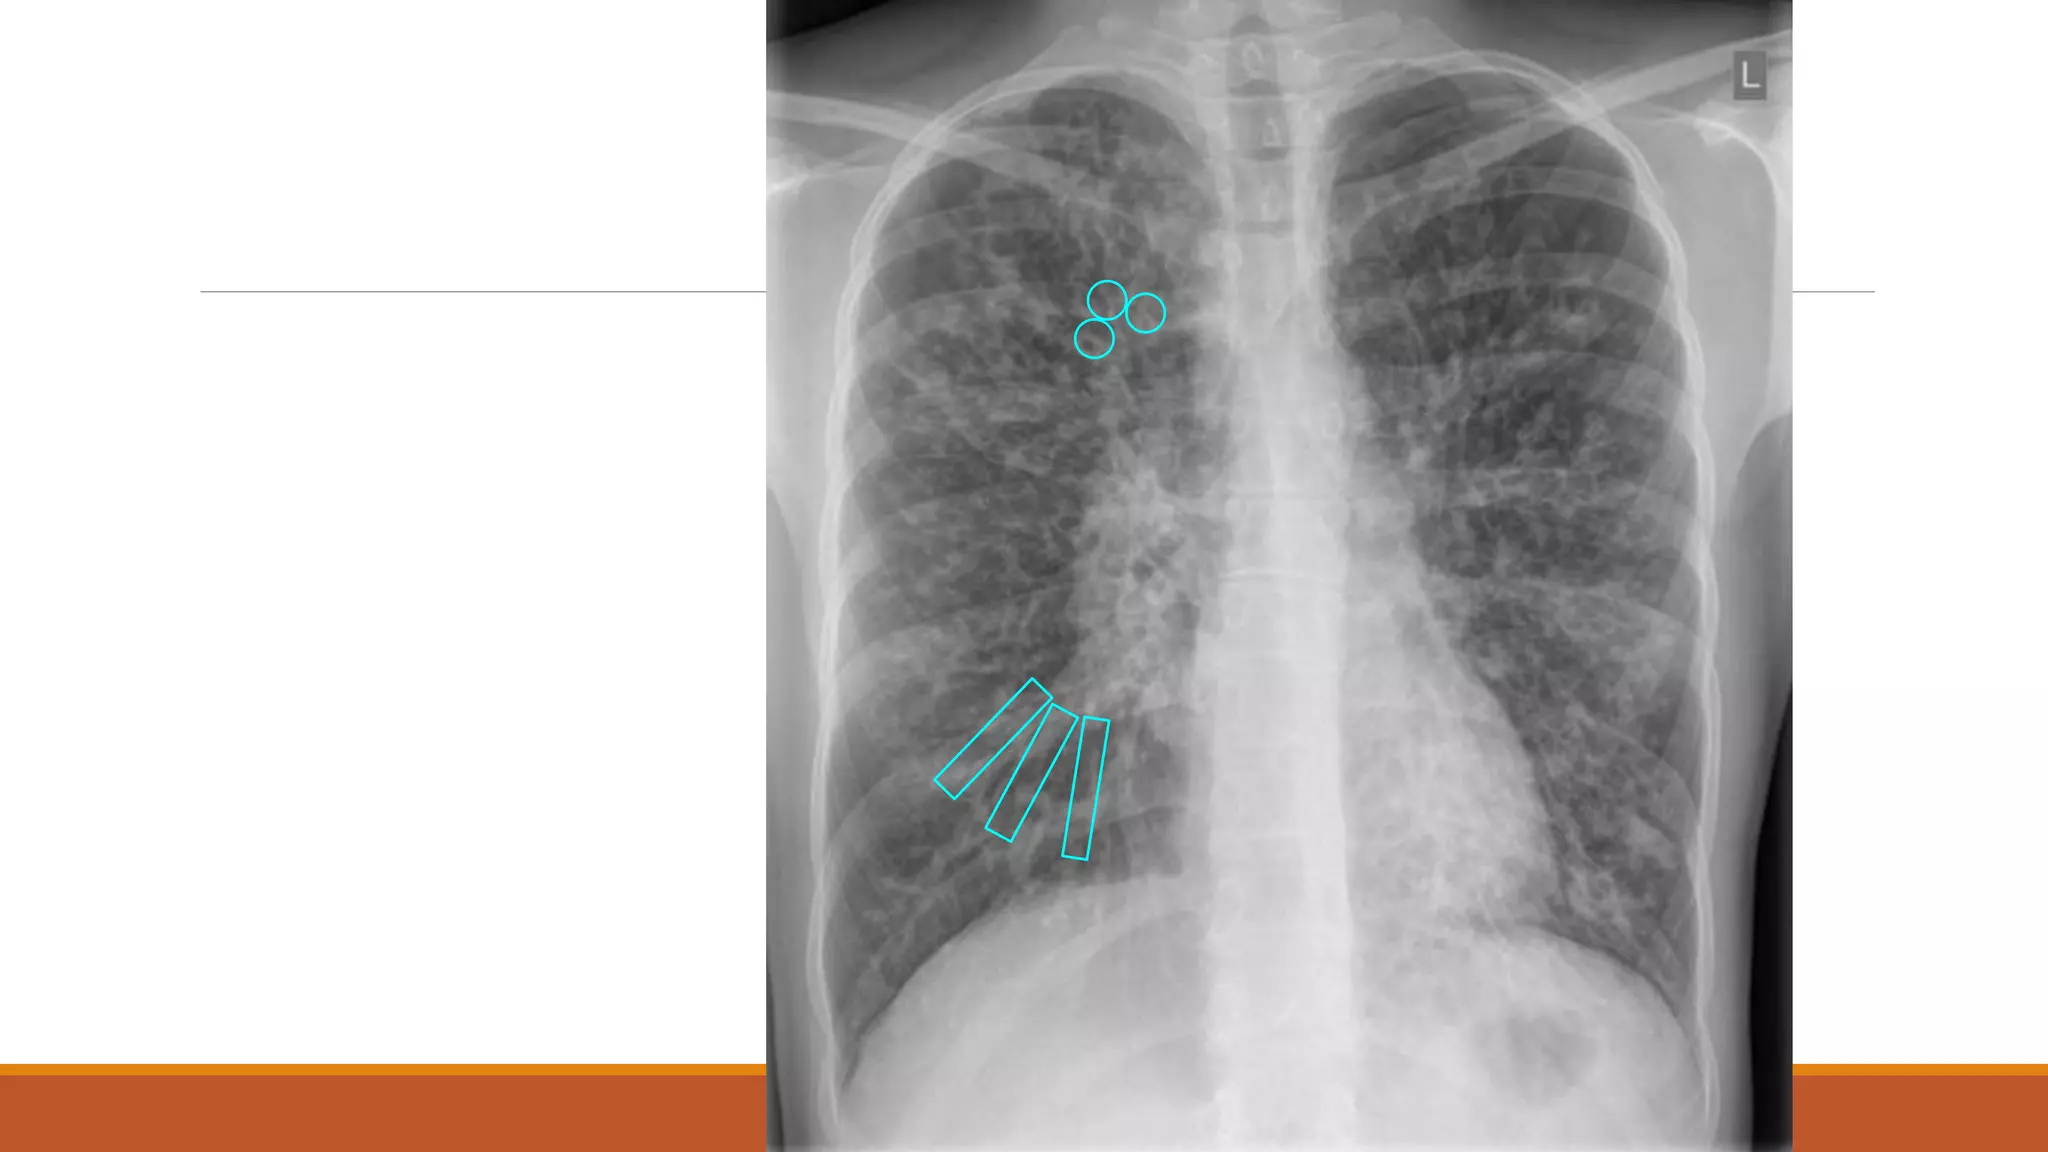

Plain radiographic signs of bronchiectasis

•In most cases.Normal

•Tram track shadows

•Signet ring shadows

Specific

findings of

bronchial

dilatation

• Peribronchial cuffing (thickened hazy bronchial wall).

• Finger in glove opacities (mucus filled bronchi).

• Multiple air fluid levels (fluid filled bronchi).

Non

findings

Mucoid impaction

Fluid filled bronchi

•Signet ring sign (broncho-arterial ratio > 1).

•Lack of bronchial tapering.

•Abnormal bronchial contour.

•Visibility of peripheral air ways.

Signet ring sign

broncho-arterial ratio > 1